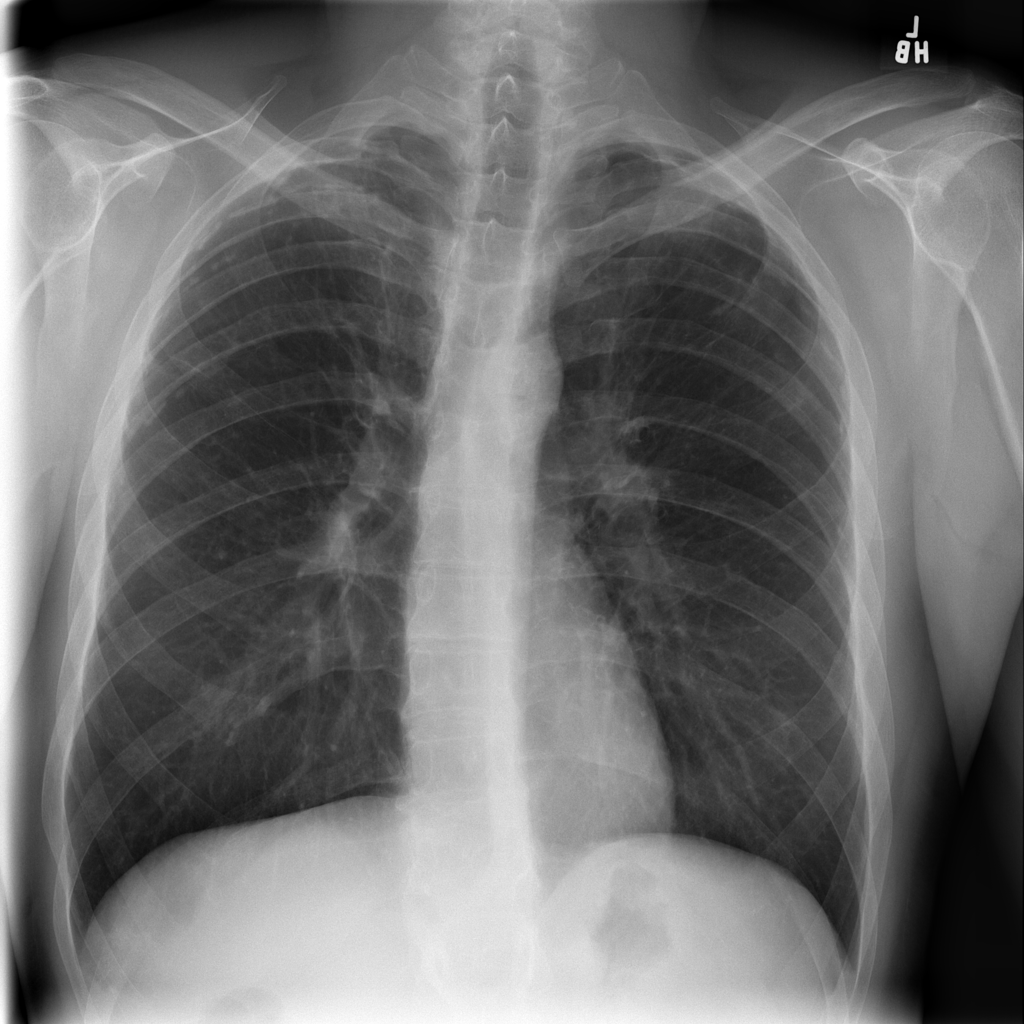

PAT-0E82 · IMG-000Emphysema

PAT-0E82 · IMG-000

AP